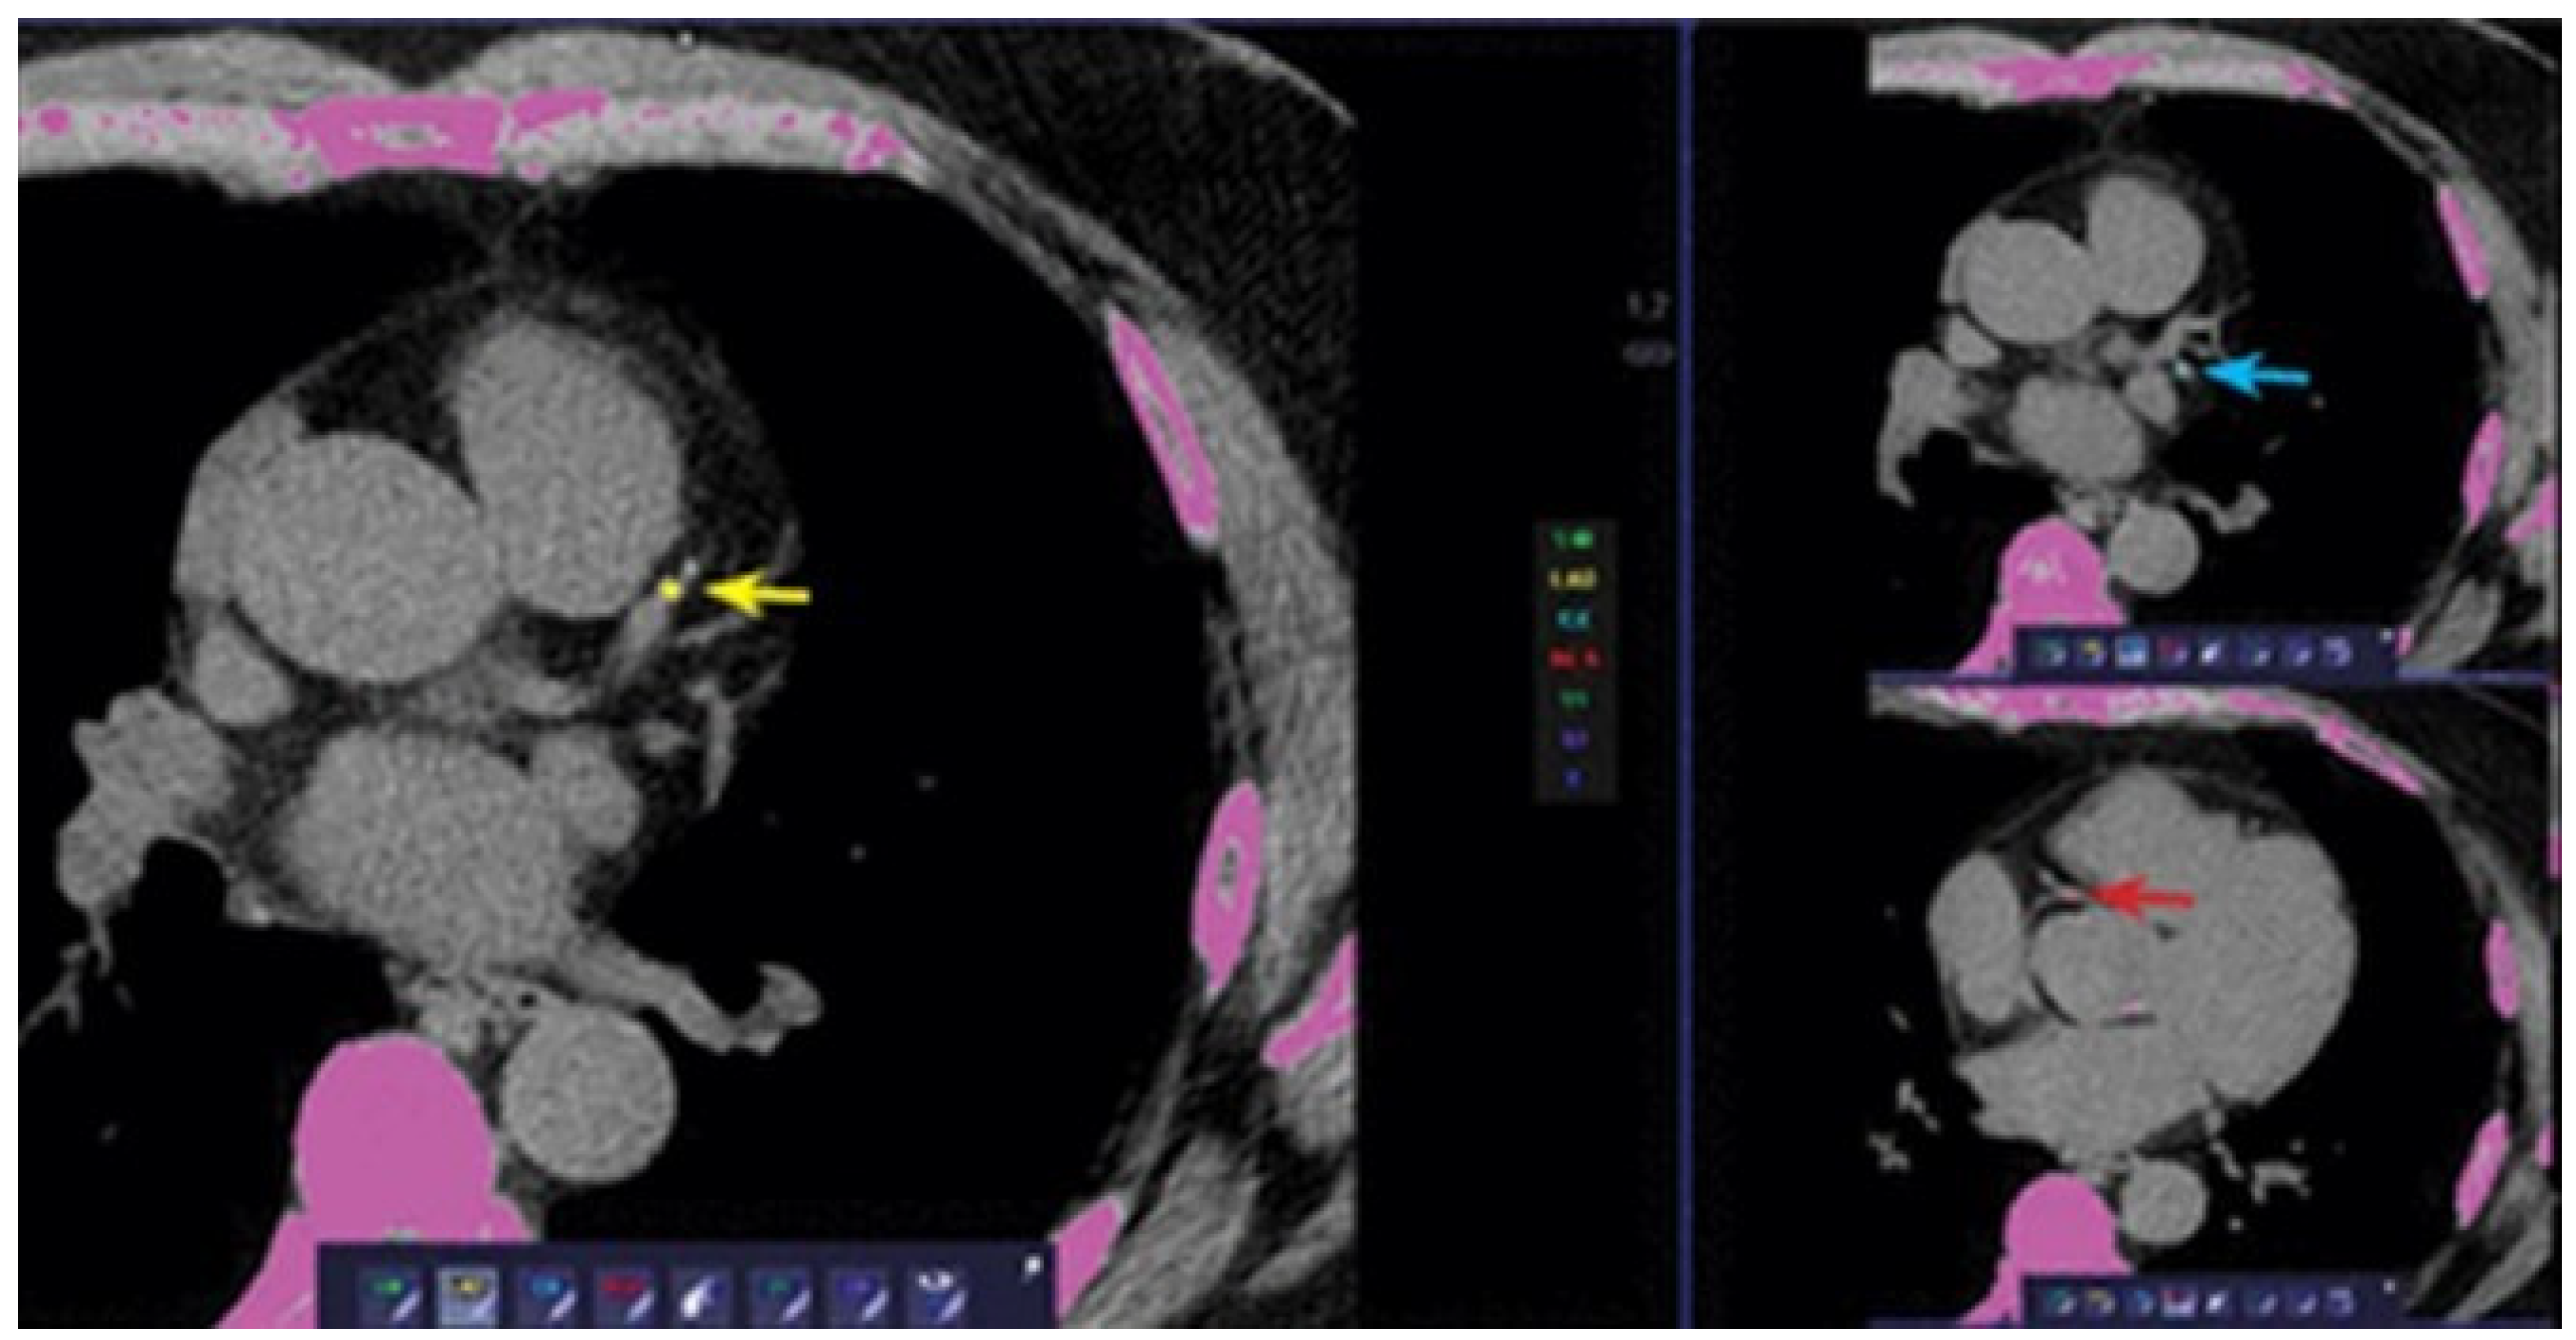

3. Perivascular Fat Attenuation Index

3.1. Definition

3.2. Measurement